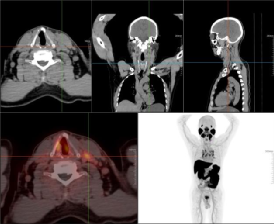

老年男性,前列腺增生病史,发现左侧颈部肿块多年,排尿困难,分叉5年,血精,怀疑前列腺肿瘤。PET/CT图如下。第一排为CT图,第二排分别为融合图、MIP图。

左侧颈部、颌下腺下后方、纵隔内(2R、4R、4L、5、6、7、8)及双侧肺门多发肿大淋巴结影,大者位于左侧颈部,最大截面约28.5mmX20.0mm,放射性摄取增高,SUVmax6.80,左侧颌下腺受压移位,考虑淋巴结转移灶,建议穿刺病理检查。

前列腺体积增大,并向前上凸入膀胱,腺体密度欠均匀,最大横径约55.3mm,前后径约42.5mm,腺体内点、条状高密度影,放射性摄取局限性增高,腺体中央部和外周部为著,摄取增高范围约38.1mmX27.3mm,SUVmax7.09,前列腺包膜局部略毛糙,考虑前列腺Ca,肿瘤突破包膜不除外。